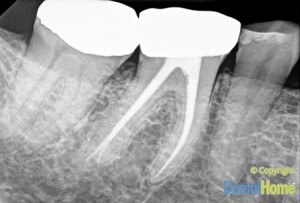

Esto requiere una limpieza y desinfección del conducto radicular realizando un llenado con un producto llamado gutapercha.

La endodoncia se realiza para que el diente no pase del color blanco al negro, no vuelva a doler y se eliminen bacterias que puedan afectar el hueso posteriormente.